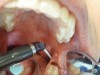

The angled handpiece of the CO2 laser was held perpendicular to the target lesion (Figure 4) and the ablation of the inflamed tissue began (Figure 5). The dental surgeon was careful to avoid contact between the laser beam and the tooth enamel. (Note: In this case, the inflamed tissue was located distally from the involved molar. There was no direct contact of the beam with the tooth, as the surgeon was careful not to hit the enamel. However, if an operculum covers part of the tooth, an adaptive tool (for example, a wax spatula) needs to be inserted between the tissue and the tooth to prevent possible damage. For an inexperienced CO2 laser surgeon, it is important and highly recommended to always shield the tooth during the procedure.6)

Fig 5. The ablation of the inflamed tissue began.

Figure 5